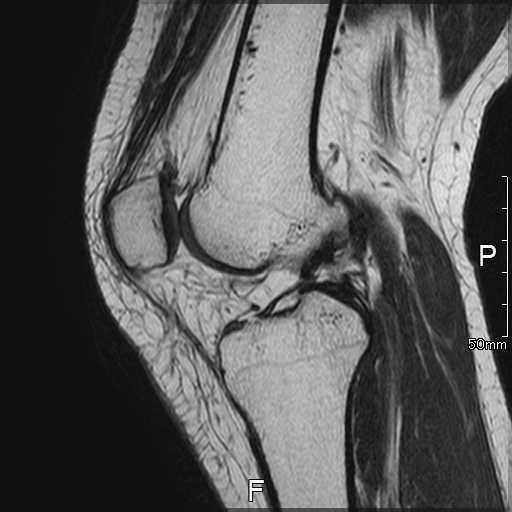

MRI所見

| 手術前 | 手術後 |

| ACLの緊張および連続性は消失している | 再建靭帯の成熟をみとめる |